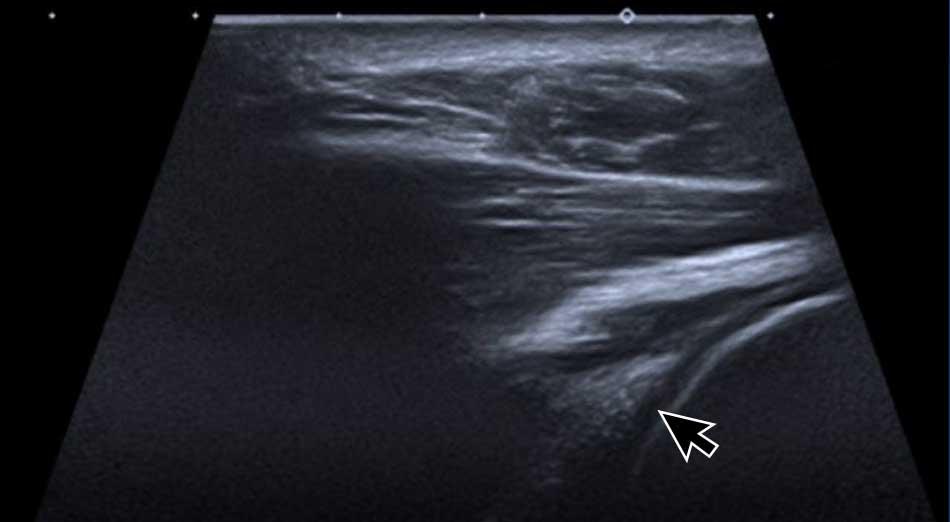

Posterior labrum and glenohumeral joint

Sụn viền sau có thể được khảo sát bằng cách đặt đầu dò

tại mặt sau của khớp ổ chảo – cánh tay.

Sụn viền được thấy như một cấu trúc tăng âm hình tam giác, có độ tăng âm cao hơn

sụn khớp lân cận (mũi tên).